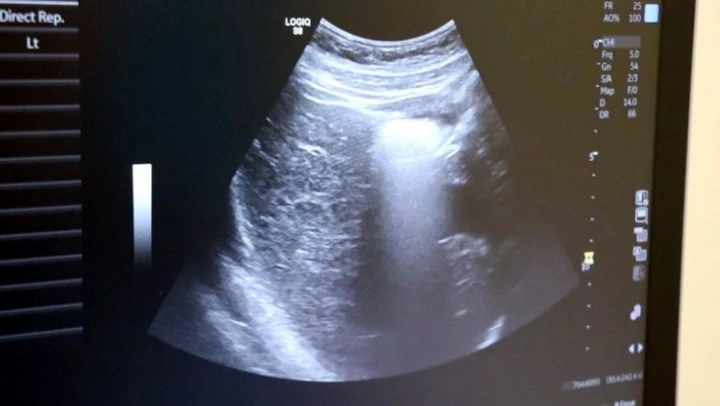

Ayrıntılı ve 4 boyutlu ultrason ile bebeklerin doğmadan önceki sağlık durumlarının belirlenebileceğine değinen Uzm. Dr. İlker Eroğlu, 'Ultrason; yüksek frekanslı ses dalgalarının bilgisayar işlemcisinde işlenip, kablo arayıcılığıyla monitöre aktarılmasıdır. Son yıllarda gebelikte ayrıntılı ultrason gerekliliği giderek artmaktadır. Yaklaşık 50 yıl önce ultrason yaygın değilken doğumlarda bebek nasıl doğacak, sağlıklı mı sağlıksız mı doğacak ya da cinsiyet bile bilinemiyordu. 4 boyutlu ultrasonda ya da ayrıntılı ultrasondan sonra bebeğin sakatlıkları doğumdan önce anlaşılıp, tedavisi mümkün olanlar da doğumdan önce tedavi edilebilir oldu. Böylelikle bebeklerin daha sağlıklı olarak dünyaya gelmesi sağlanmış oldu. O nedenle ayrıntılı ultrason gereklidir' dedi.

Renkli ultrasonlarda bebeklerin anne karnındayken sakatlığı olup olmadığının belirlendiğini ifade eden İlker Eroğlu, '4 boyutlu ultrason halk arasında 'renkli ultrason' diye bilinir. Anneler bu ultrasonda bebeğin görüntüsünü anladığı için onu daha çok sever. Hekimler genelde ultrasona siyah-beyaz bakar. 4 boyutlu ultrason iç organlar hakkında detaylı bilgi vermez. Biz detaylı ultrasonda (2. düzey ultrason) bebeğin iç organlarına yönelik incelemeyi siyah beyaz olarak yaparız. O nedenle bizim için siyah-beyaz ve 2 boyutlu olarak yapılan inceleme daha önemlidir. 4 boyutlu ultrasonda da faydalandığımız yerler vardır. 4 boyutlu ultrasonda örneğin; bebeğin kolu-bacağı yoksa, dudak yarığı varsa, gösterebiliriz. Çeşitli anatomik deformasyonları da anneye gösterebiliriz. Hala dünyada ayrıntılı ultrason 2 boyutlu ve siyah-beyaz olarak yapılır' diye konuştu.